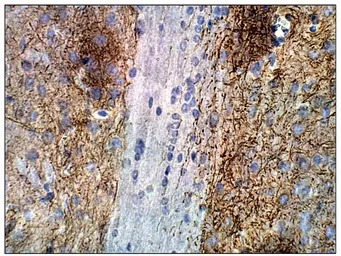

IHC-P analysis of mouse brain tissue using GTX14777 Adenylate cyclase 2 antibody.

Dilution : 1:50